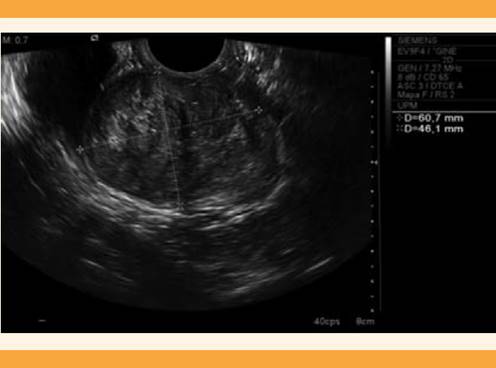

Después de algunos meses acudió, nuevamente, a consulta médica, indicando un incremento significativo de los síntomas, entre los que destacaron importantes molestias vaginales, metrorragias mayores al ciclo menstrual y dispareunia, por lo que se decidió repetir el estudio ecográfico (Figura 1y2) y complementarlo con resonancia magnética para mayor definición. La tumoración aumentó notoriamente de tamaño (58 x 57 x 60 mm), con forma redondeada y aspecto sólido, zonas de hiperseñal en su espesor, quizá por la coexistencia de estructuras venosas y áreas de degeneración mixoide. No se identificaron otros cambios que sugirieran malignidad. La tumoración se encontraba en el espacio vesicovaginal, al parecer dependiente de la pared anterior vaginal, aislada del cuello uterino y del útero, pero sugerente de compresión de la pared posterior de la vejiga urinaria (Figura 3). Con estos datos se estableció el diagnóstico de leiomioma vaginal pediculado. Debido a los signos y síntomas se inició el tratamiento con acetato de ulipristal (5 mg al día) para disminuir el volumen y sangrado miomatoso. Después de dos ciclos de tratamiento la tumoración se incrementó a 70 x 55 mm, por lo que se solicitó la participación multidisciplinaria del servicio de Urología y en común acuerdo se decidió la miomectomía por vía vaginal, esta vez con consentimiento de la paciente.

Figura 1 Ecografía transvaginal de una masa redondeada y homogénea, de 60 x 46 x 48 mm, en la cara anterior de la vagina, de aspecto miomatoso.